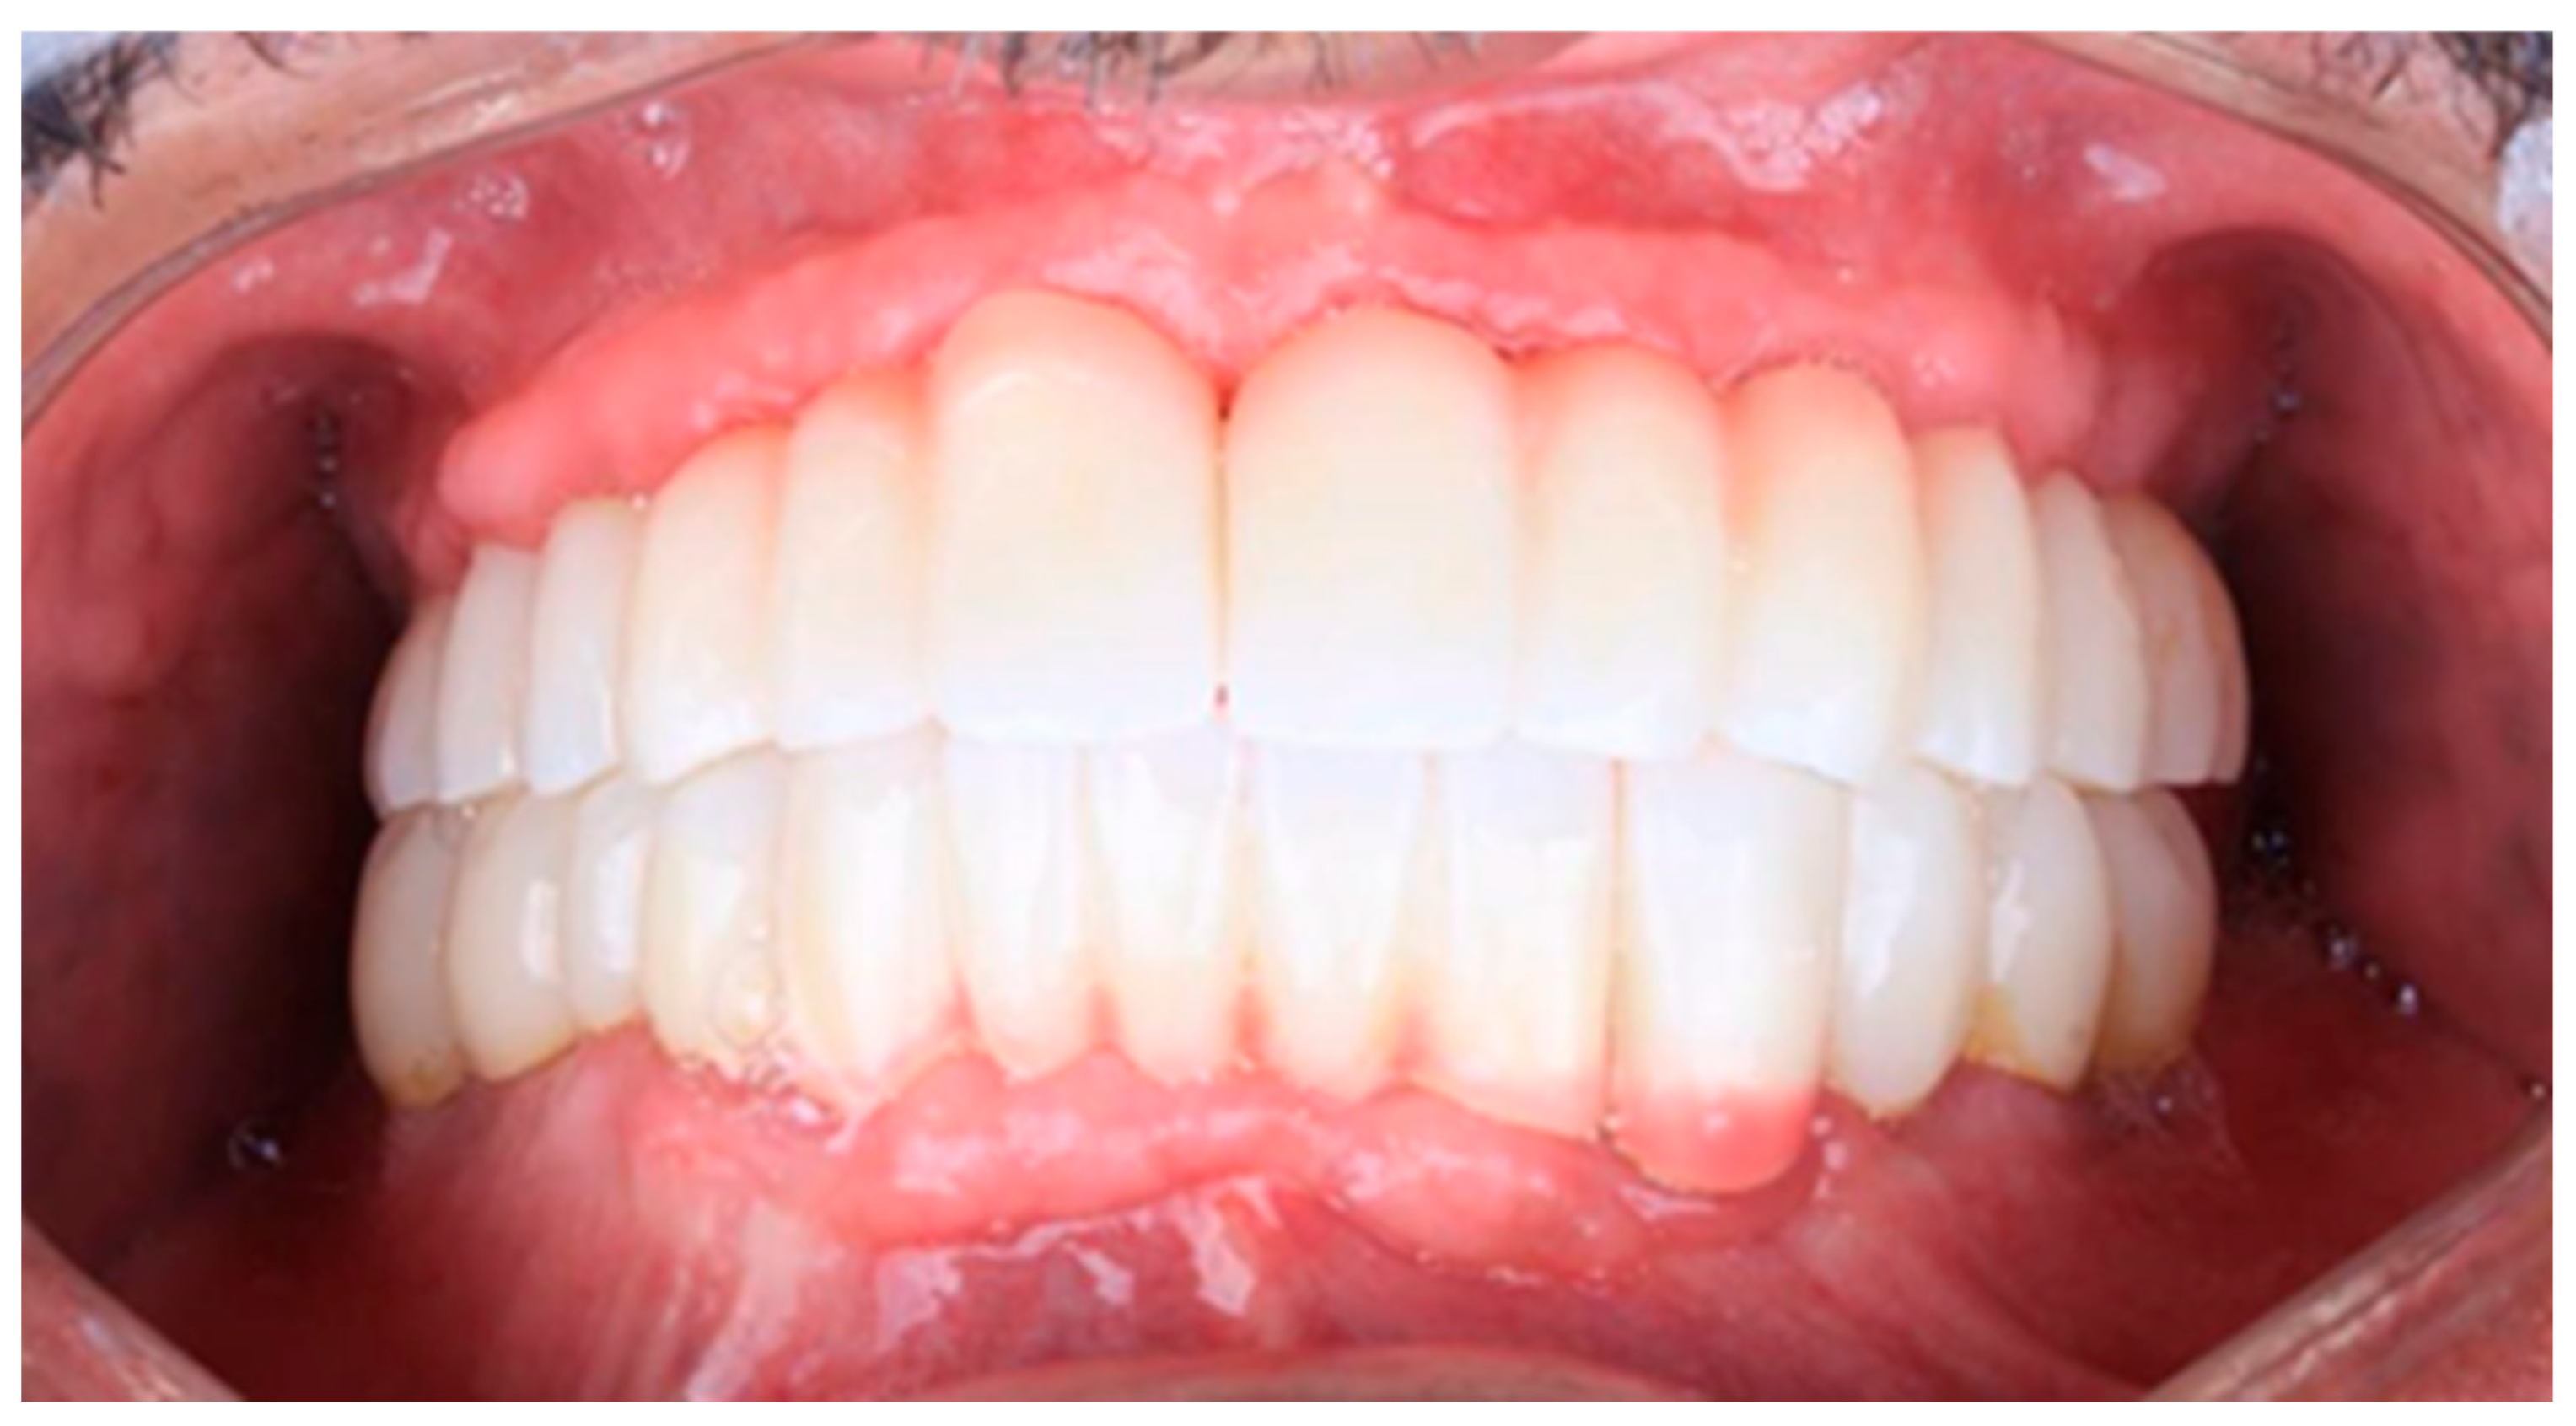

2.6. Sixth Visit

Figure 16. Follow-up photo.